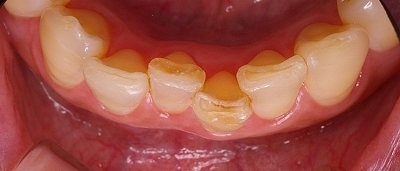

下顎歯列の凸凹の矯正治療

下顎の全体です。

前歯や小臼歯が歯列弓の中に納まりきれない状態です。

前歯の歯並びのバランスを考えるとスペースがどうしても足りません。

きれいに並びきれないので前歯一本をやむを得ず抜歯しました。

歯列全体にワイヤーをかけて矯正力をかけます。

少しずつゆっくりと歯列弓を拡大していきます。

小臼歯の並ぶスペースが確保できてきました。

矯正治療で歯並びが良くなる事は審美的な改善だけではなく歯周病や虫歯になるリスクを軽減します。

凸凹があるとプラーク(汚れ)が凹の部分に停滞しやすいのです。

歯ブラシが届きにくいのできれいに磨くのが困難です。

歯並びが整いました。

これなら歯ブラシが届きやすいのできれいに磨けます。